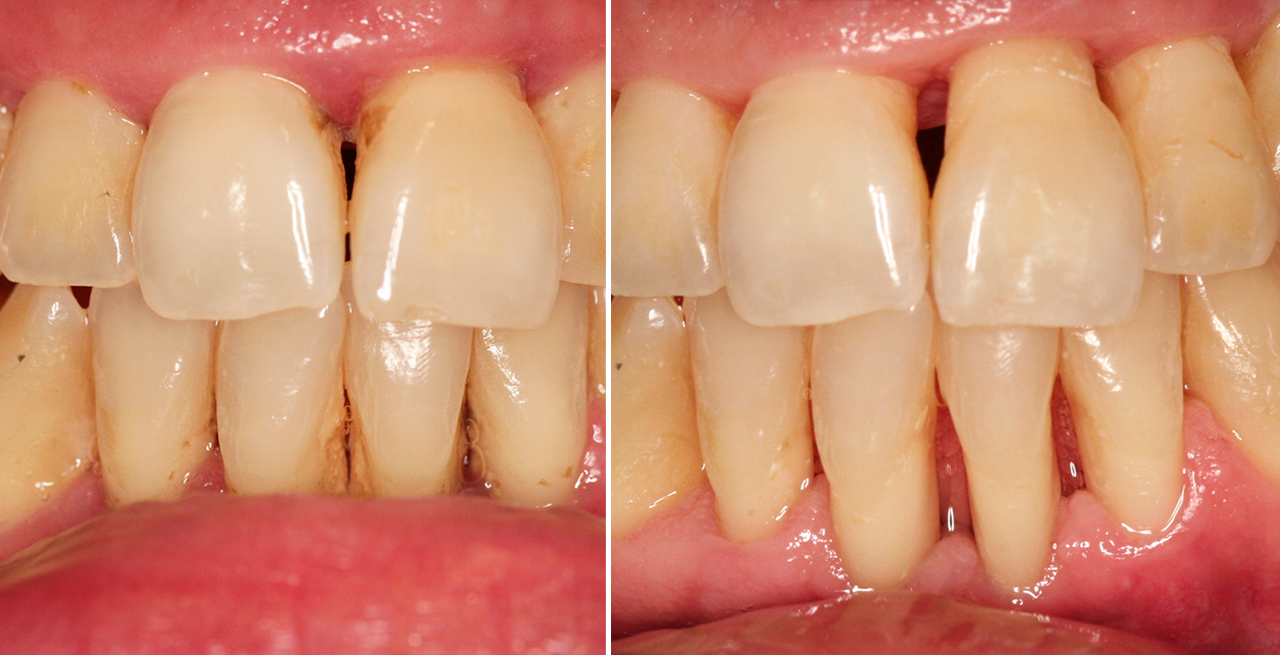

Plano de tratamento: Colocação de 4 implantes superiores e 2 implantes inferiores. Confeção de uma barra superior e colocação de 2 locators® na parte inferior. Confeção de uma prótese superior e outra inferior removível, com encaixes na barra e locators®.

A escolha deste plano de tratamento deve-se ao facto de o paciente querer uma solução total, mas não completamente fixa, uma vez que não tinha muita destreza manual para higienizar uma prótese fixa. Desta forma, conseguiu uma solução bastante retentiva (devido aos encaixes) mas que consegue remover para uma higienização correta.